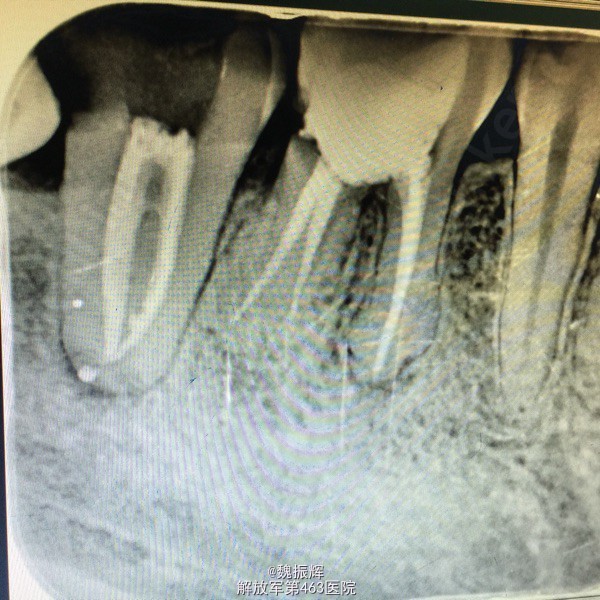

患者毕某,女性,右下后牙不适数日。数日来右下后牙自发痛影响睡眠,影响进食,来院就诊。

查体:47远中邻面龋坏,探(+),冷(+),叩(-),X线示远中龋坏近髓,48近中阻生,47,48之间食物嵌塞。

诊断:牙髓炎 处理:局麻下,47降牙合,去腐,开髓,揭髓顶冲洗,拔髓,根管疏通测量及机用镍钛器械进行根管预备,次氯酸钠进行根管冲洗,大椎度牙胶尖试尖,进行根管充填。Zoe暂封,观察嵌体修复。择期拔除48。